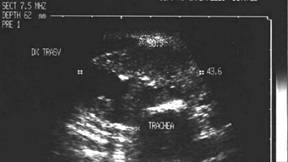

Lob stang, proiectie trasversala si longitudinala

Barbat de 55 ani. Formatiune nodulara voluminoasa ce ocupa 2/3 din lobul stang, hipoecogena, neomogenea, de 20 x 23 x 44mm(10 cc). Citoaspirata ecoghidata: carcinom midolar. Confirmat histologic.

Scintigrafia si CT aceluiasi pacient, metastaza laterocervicala stg ce impinge traheea spre dr.